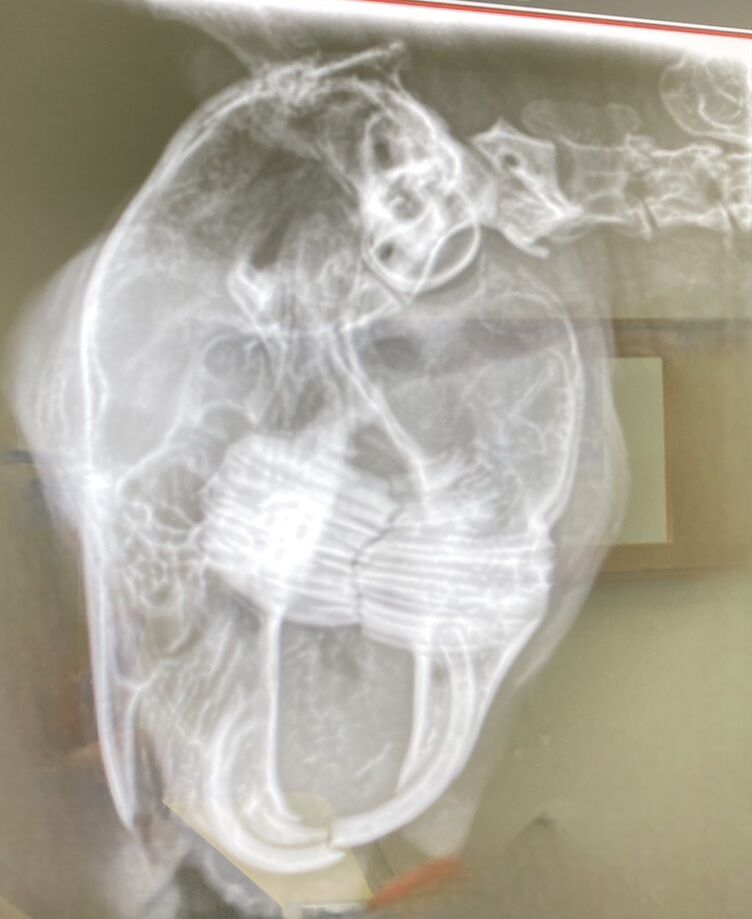

寿ちゃん【佐渡っこ】

保護後、心筋症と判明し治療を続け、現在の心臓の状態は落ち着いていますが、投薬と定期検査は継続中

6/21 心検診 お薬継続で次回レントゲンの予定です